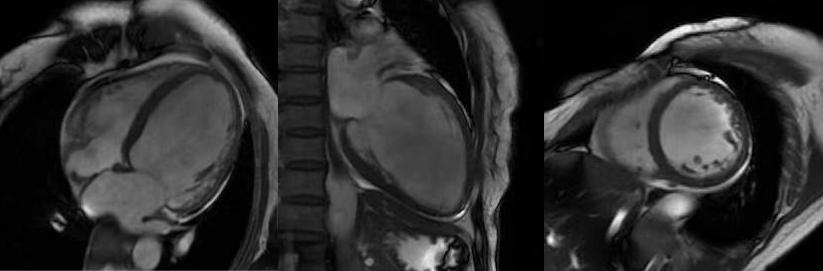

非缺血性心肌?。簲U張型心肌病、肥厚型心肌病、高血壓性心肌病、心肌淀粉樣變、心肌過度小梁化、限制性心肌病、心臟結節(jié)病、心肌炎等,心肌呈現(xiàn)不同程度條狀、斑片狀、斑點狀的延遲強化。

擴張型心肌病

肥厚型心肌病,舒張末期心尖形似“黑桃A征”